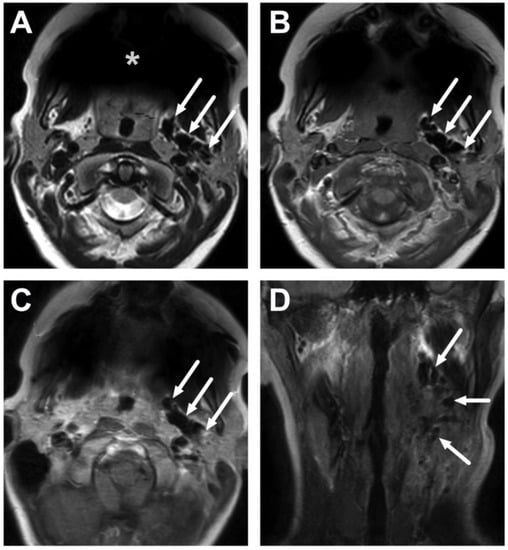

5.1. Lymphadenitis with Purulence vs. Necrosis

5.3. Artifacts

6. Complications

6.1. Mediastinitis